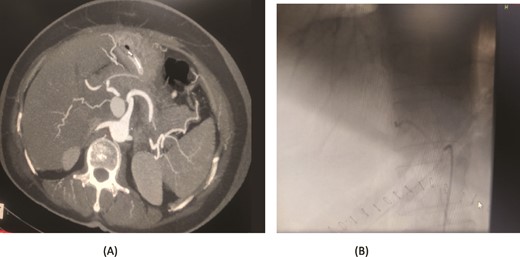

A 57-year-old female underwent a distal pancreatectomy for a pancreatic neuroendocrine tumo. On the 13th postoperative day, the patient presented in a state of shock and intraperitoneal bleeding. A contrast-enhanced CT angiogram revealed the presence of a pseudoaneurysm originating from the splenic artery. The patient underwent endovascular coil embolization of the splenic artery and bleeding stopped and was discharged 3 days following the procedure (Fig. 1).

Case 1. (A) Angiogram pseudoaneurysm from splenic artery. (B) Angioembolization of splenic artery with coil